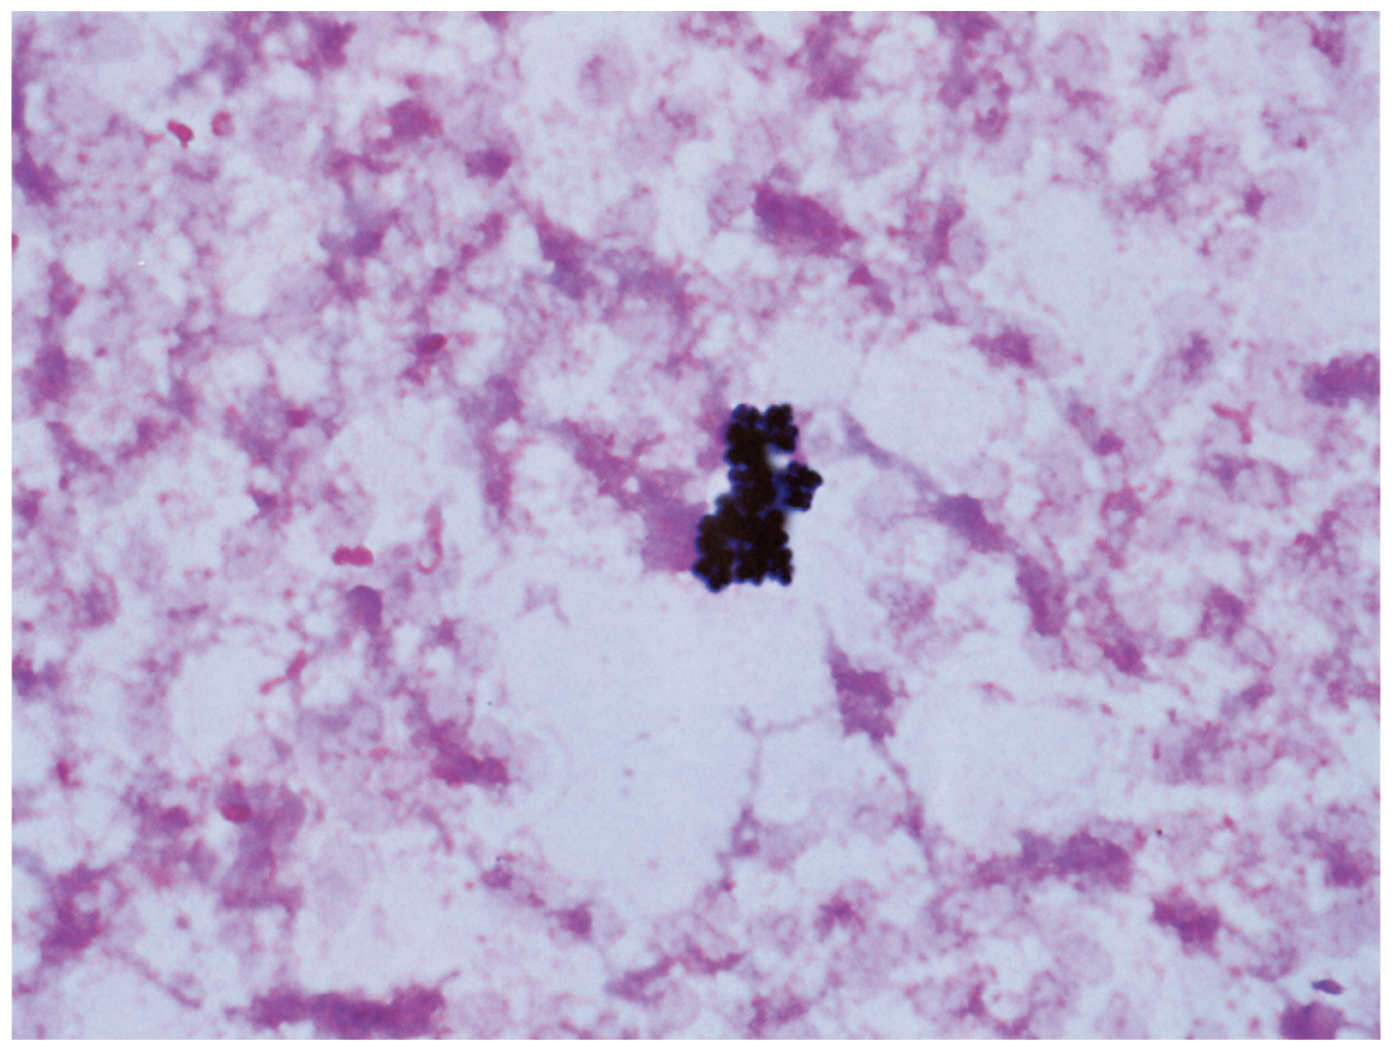

65歳の男性。胃癌術後で入院中である。手術後から経口摂取が困難なため,右内頸静脈に中心静脈カテーテルを留置して中心静脈栄養を行っている。術後12日目に発熱を認めた。発熱の他に新たな症状はない。意識は清明。体温38.1℃。脈拍100/分,整。血圧124/60mmHg。呼吸数18/分。SpO2 97%(room air)。眼瞼結膜と眼球結膜とに異常を認めない。中心静脈カテーテル刺入部に異常を認めない。心音と呼吸音とに異常を認めない。手術創の表面に異常を認めない。腹部は平坦,軟で,圧痛を認めない。肋骨脊柱角に叩打痛を認めない。手指や足趾に異常所見を認めない。全身状態は安定しており,胸腹部単純CTで発熱の原因精査を行ったが,熱源は判明しなかった。血液培養2セットを採取したところ,翌日2セットともに陽性となった。血液培養ボトル内容のGram染色標本を下に示す。

抗菌薬を投与することにしたが,その前に行うべき対応はどれか。